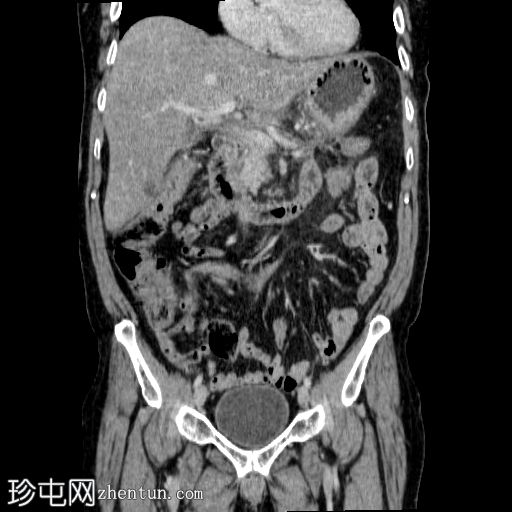

轴向C+门静脉期

8.jpg

胰体尾弥漫性增大,特征为胰腺实质低强化,无明显坏死区域。

该病灶与以下表现相关:

胰周筋膜平面边界不清的污迹,无明显壁形成、气室、固体碎片或血液产物。

多个亚厘米大小、非特异性的腹主动脉旁淋巴结和肠系膜淋巴结,可能具有反应性。

病变范围如下:

病变横向延伸至左前肾旁间隙,伴有Gerota筋膜增厚。

病变向下延伸至盆腔。

无肠系膜或脾脏血管阻塞的证据。

未见导管扩张或钙化。